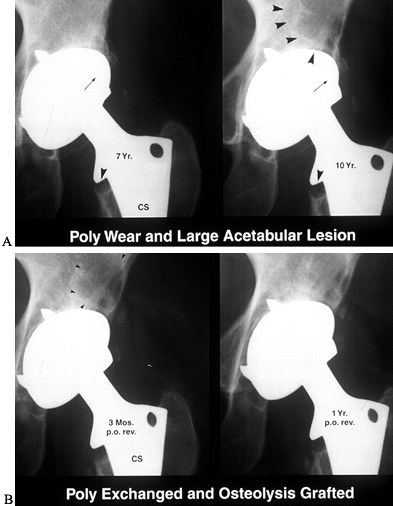

![]() |

Figure 106.4. A: Polyethylene wear leading to large supra-acetabular lesion. Note asymmetric position of the head in the cup. B: Cup is stable; therefore, retained and osteolytic lesion grafted with good results.